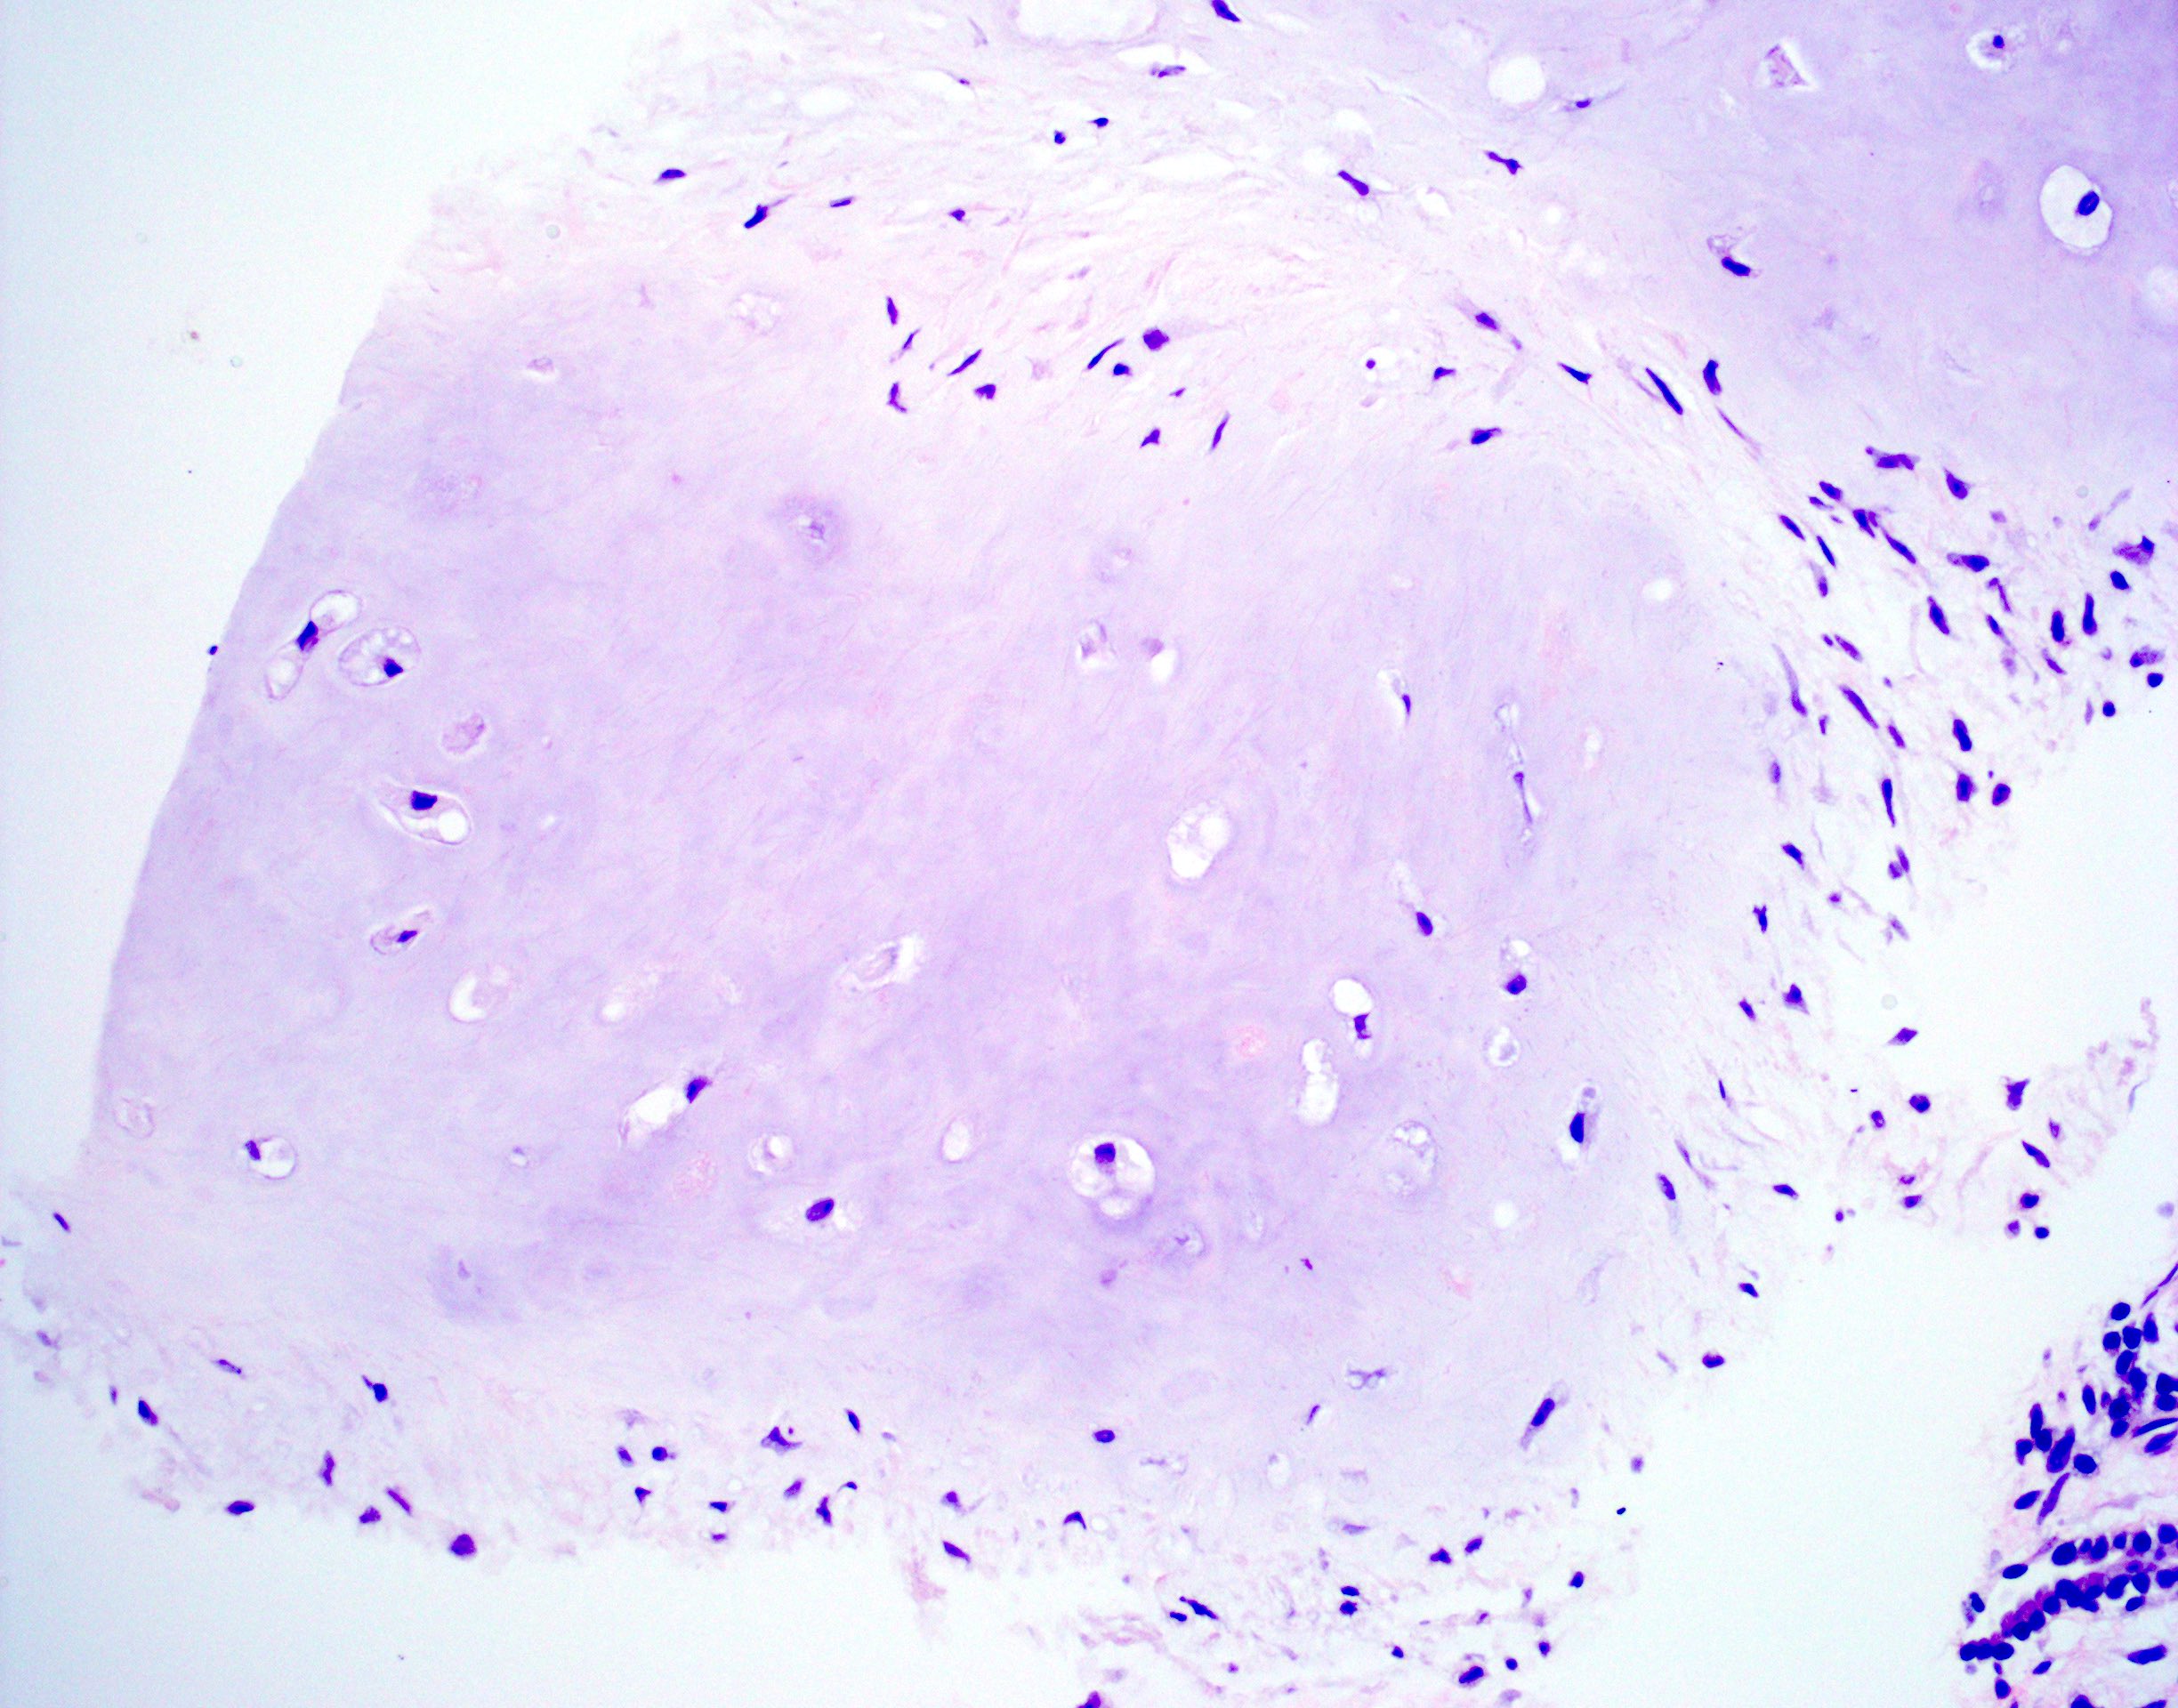

Microscopic (histologic) description

- Composed predominantly of varying degrees of mesenchymal tissue: hyaline cartilage, fat, smooth muscle and bone

- Other connective tissue elements may be present, represented by bland spindle cells, fibrous tissue or myxoid change

Microscopic (histologic) images

Contributed by Hui-Hua Li, M.D., Ph.D. and Jefree J. Schulte, M.D.

Contributed by @Andrew_Fltv on Twitter